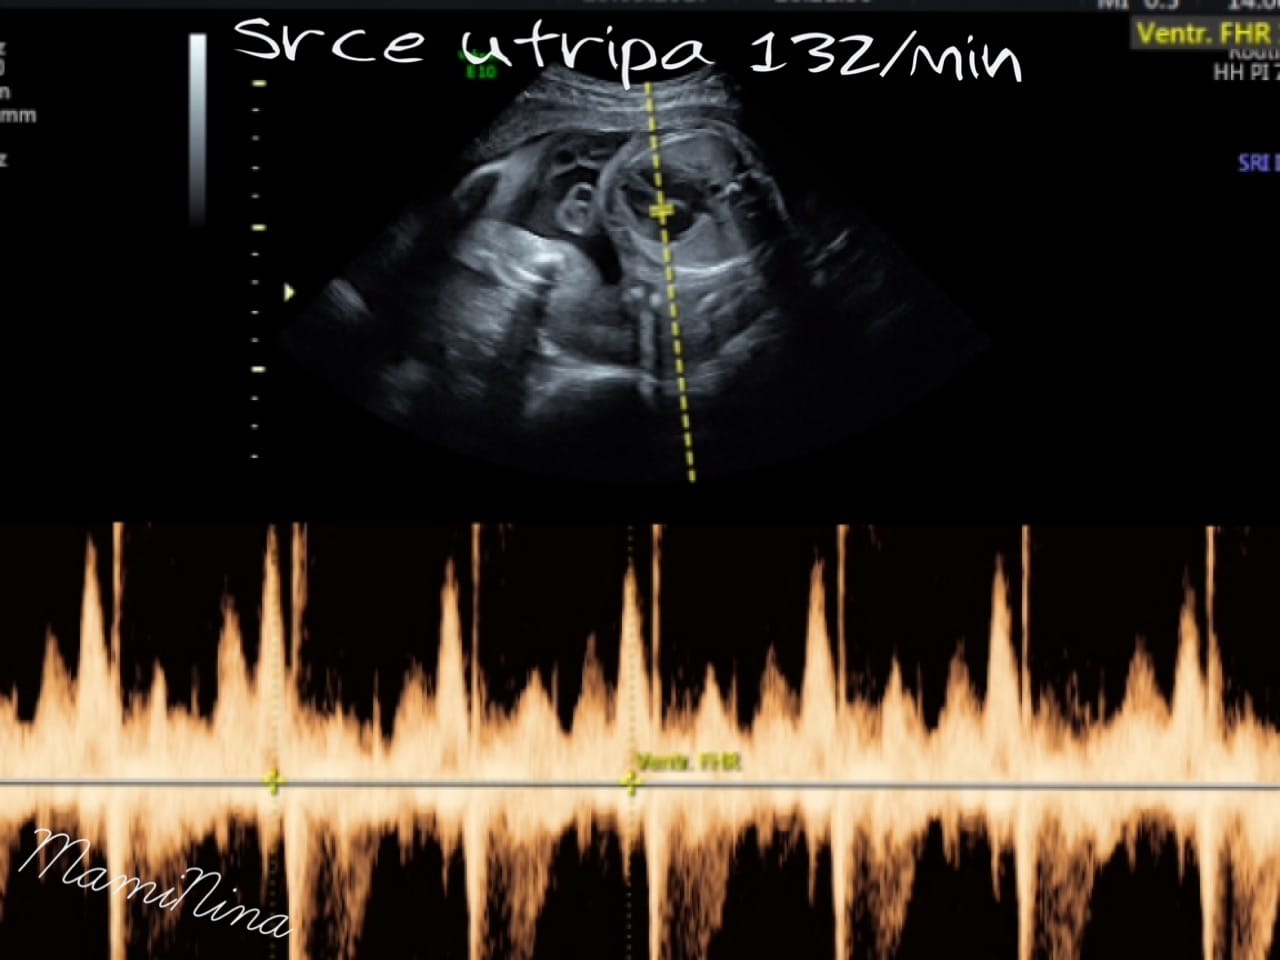

Pogledali smo v njeno glavico, preverili srček, nogice, rokice, obrazek, mehur in na sploh vse. In vse izgleda prav super.

Srček utripa z 132 udarci, mala pa ima že približno nekje 830 g (če bo teža naraščala tako kot do sedaj, predvidevam, da bo precej lahka, seveda pa so tudi njene mere manjše).